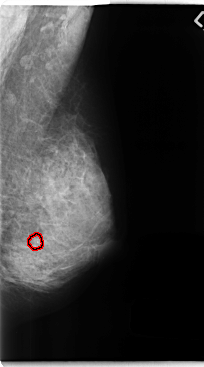

C_0257_1.LEFT_MLO

FILE: C_0257_1.LEFT_MLO.OVERLAY

TOTAL_ABNORMALITIES 1

ABNORMALITY 1

LESION_TYPE CALCIFICATION TYPE ROUND_AND_REGULAR DISTRIBUTION CLUSTERED

ASSESSMENT 3

SUBTLETY 5

PATHOLOGY BENIGN

TOTAL_OUTLINES 1

BOUNDARY

LEFT_MLO LINES 4768 PIXELS_PER_LINE 2640 BITS_PER_PIXEL 12 RESOLUTION 50 OVERLAY